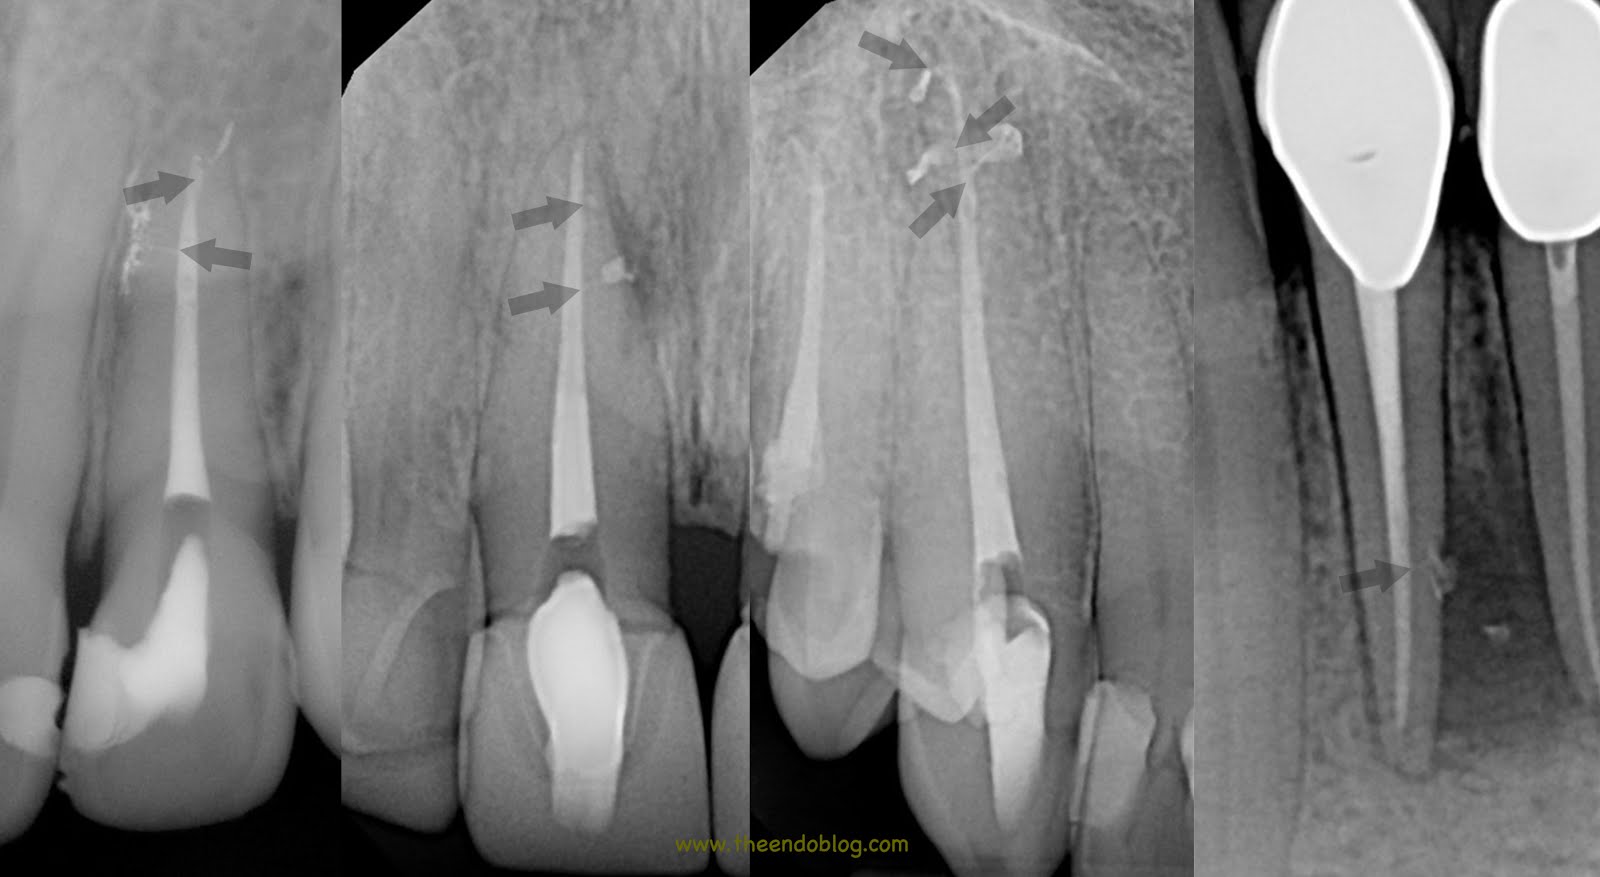

From www.theendoblog.com

The Endo Blog The Buzz About Endodontic Irrigation Irrigation Tooth Extraction There are various choices for the extraction of causative tooth or root canal treatment; Routine irrigation with chlorhexidine after the extraction of third molars helps to reduce pain and lowers the incidence of alveolar osteitis. Third molars may need to be extracted for various reasons, including: Pericoronitis of partially impacted teeth; This technique reduced halitosis, improved plaque and. These include. Irrigation Tooth Extraction.